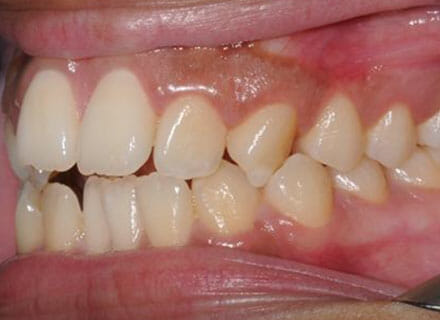

This patient came to us because she hated her smile: it was too narrow, the upper front teeth were all crowded into each other and twisted. She couldn’t eat a sandwich properly with the front teeth because of the gap – the open bite. We were able to expand both jaws to make space to align all the teeth without having to extract – in about 18 months using clear brackets.